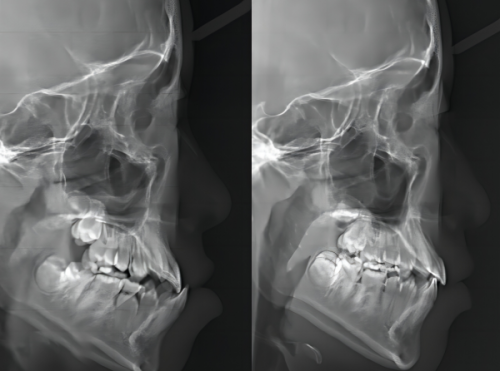

上海尤旦忆兴口腔门诊部(普陀泾阳路店)拥有专精的医生团队,他们具备丰富的临床经验和扎实的专精知识。在治疗过程中,医生会根据患者的具体情况制定个性化的治疗方案。例如,对于龋齿患者,医生会采用精良的补牙技术,不仅能有效修复牙齿,还能减少患者的疼痛感。对于牙周炎患者,医生会进行系统的牙周治疗,帮助患者修复口腔健康。对于牙齿不齐的患者,门诊部提供多种矫正方案,如传统金属矫正、隐形矫正等,满足不同患者的需求。

许多患者在上海尤旦忆兴口腔门诊部(普陀泾阳路店)接受治疗后,都给出了高度评价。患者小李因龋齿疼痛难忍来到这里,医生耐心地为他检查,并快速制定了治疗方案。治疗过程中,医生操作熟练,小李几乎没有感觉到疼痛。治疗后,小李的牙齿修复了正常,他对门诊部的服务非常满意。患者小张则是因为牙齿不齐前来矫正,医生根据他的情况为他选择了隐形矫正方案。在矫正过程中,医生定期为他检查,调整矫正方案。经过一段时间的矫正,小张的牙齿变得整齐美观,他对治疗成效十分惊喜。